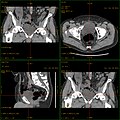

Koronal reformatierte Darstellung von Abdomen und Becken; gut zu erkennen sind u. a. die Leber und die beiden Nieren. -

Kombination aus multiplanarer Reformatierung und sliding thin slab. Der Bildkursor befindet sich in der Harnblase. Die Originalschichtdicke beträgt 1,25 mm, dargestellt wird in allen Ansichten gemittelt (= average) in 3,7 mm bzw. 3,8 mm Dicke. -